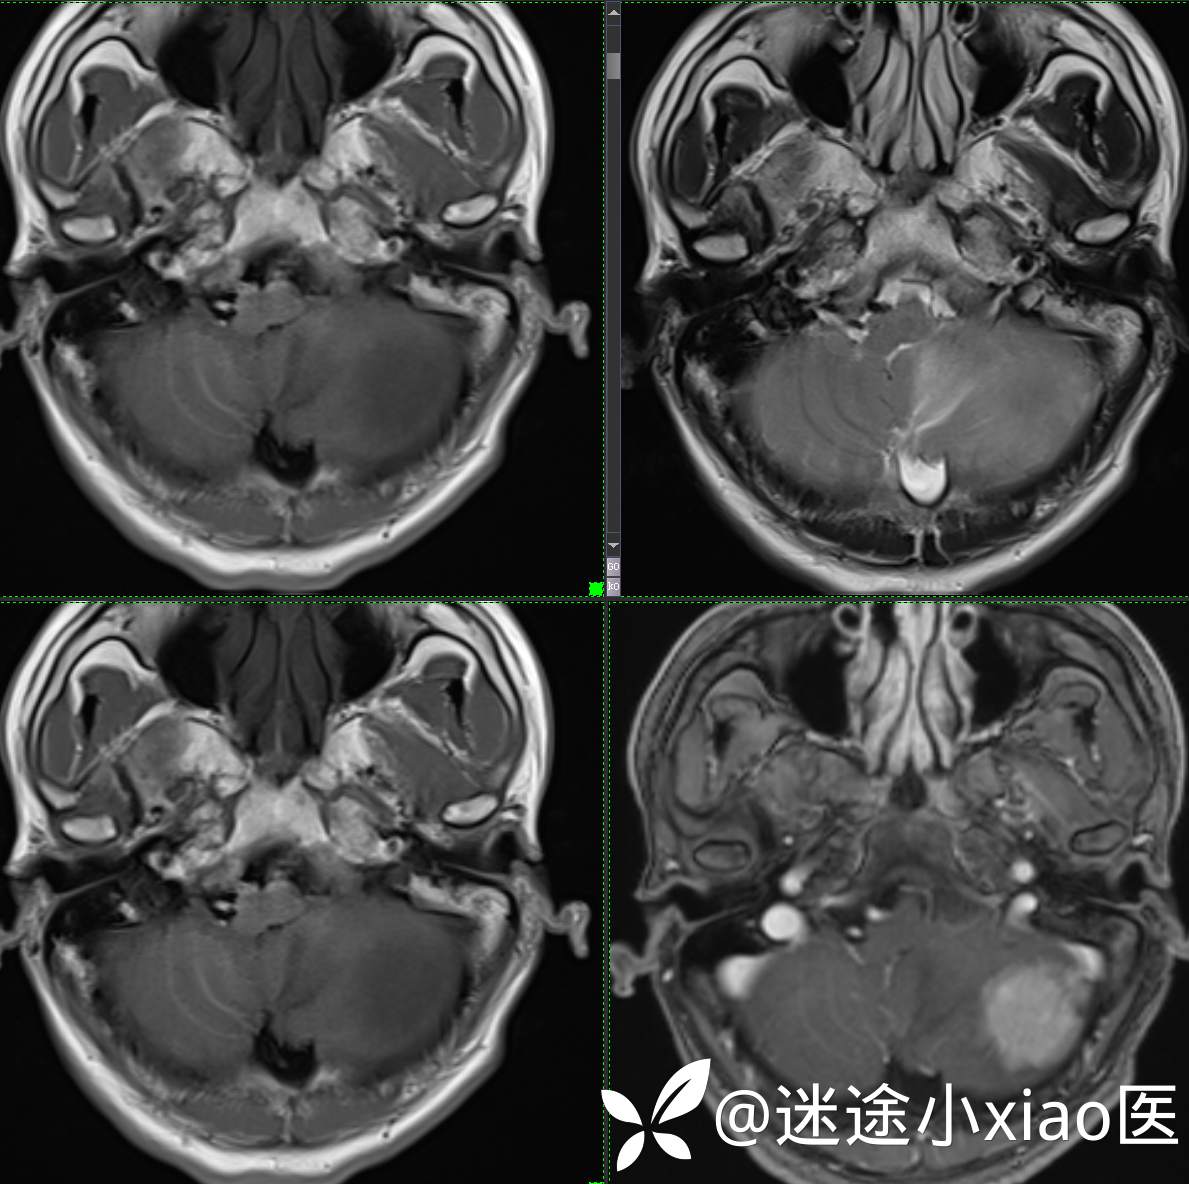

头颈组15:男,62岁,左侧小脑半球占位,原发?转移?是否有意外?

主 诉: 头晕、恶心呕吐半月余。

现病史: 患者半月前无明显诱因下明显头晕,伴恶心呕吐,无意识丧失、无智力明显下降,无视物模糊,无耳鼻腔出血,无四肢抽搐、畸形,无胸闷气促、呼吸困难。

既往:膀胱癌手术史。